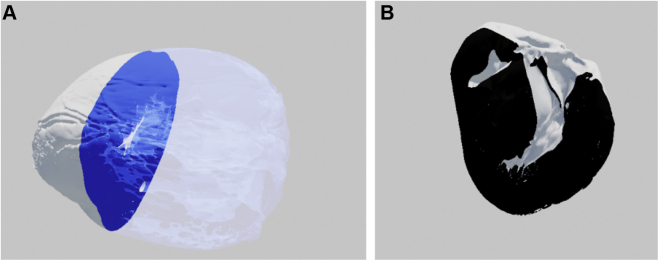

Figure 7.

Three-dimensional model of the heart in (A) short-axis and (B) long-axis views as seen in virtual reality. The image plane in panel A is blue with a transparent silhouette of the heart on the right. The image plane in panel B is black and has no silhouette.